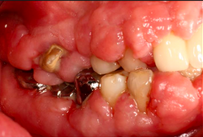

Review in 2 years

- Non-surgical periodontal therapy was performed to reduce gingival inflammation and swelling

- Surgical removal of excessive gum tissues and extraction of multiple poor prognosis teeth were carried out as well

- She was kept under strict follow up and advised to comply with meticulous oral hygiene measures throughout treatment